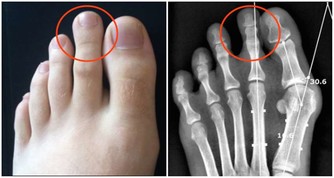

高脂血症容易導致血液黏稠,誘發炎症反應,形成動脈粥樣硬化,對腎臟造成損害;高血壓患者,腎臟的血管就會承受更多的壓力,長期下去,血管就會硬化,腎臟也會硬化;高尿酸的肥胖患者易形成結石,腎臟成為被攻擊器官之一,此外高尿酸血症也容易引發炎症反應、高血壓、高血脂等。